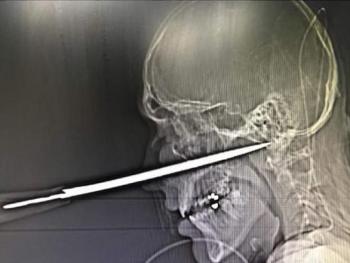

ملاكم ينجو من الموت بأعجوبة بعد أن اخترقت السكين راسه